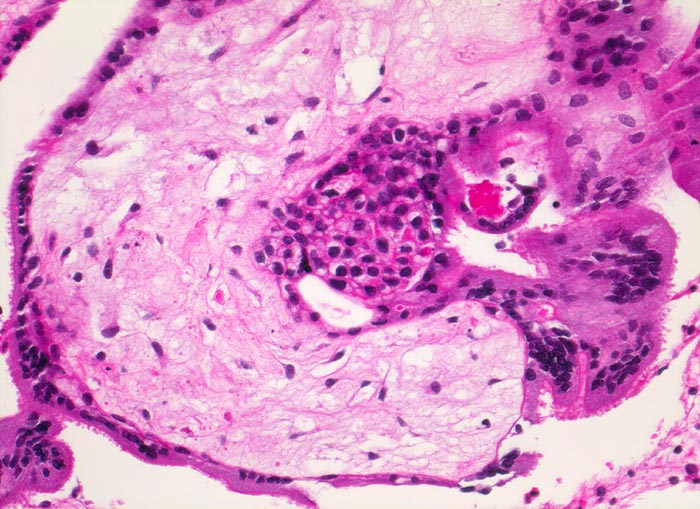

Abortkurettage: choriales Gewebe

Gefässe sind im degenerierten Zottenstroma nicht sicher zu erkennen. Die Zotte wird bedeckt von fokal leicht proliferiertem Zytotrophoblast und mehrkernigem Synzytiotrophoblast.

Missed abortion in der 11. Schwangerschaftswoche, sonographisch entsprechend der 9. Schwangerschaftswoche.

Histologie

200